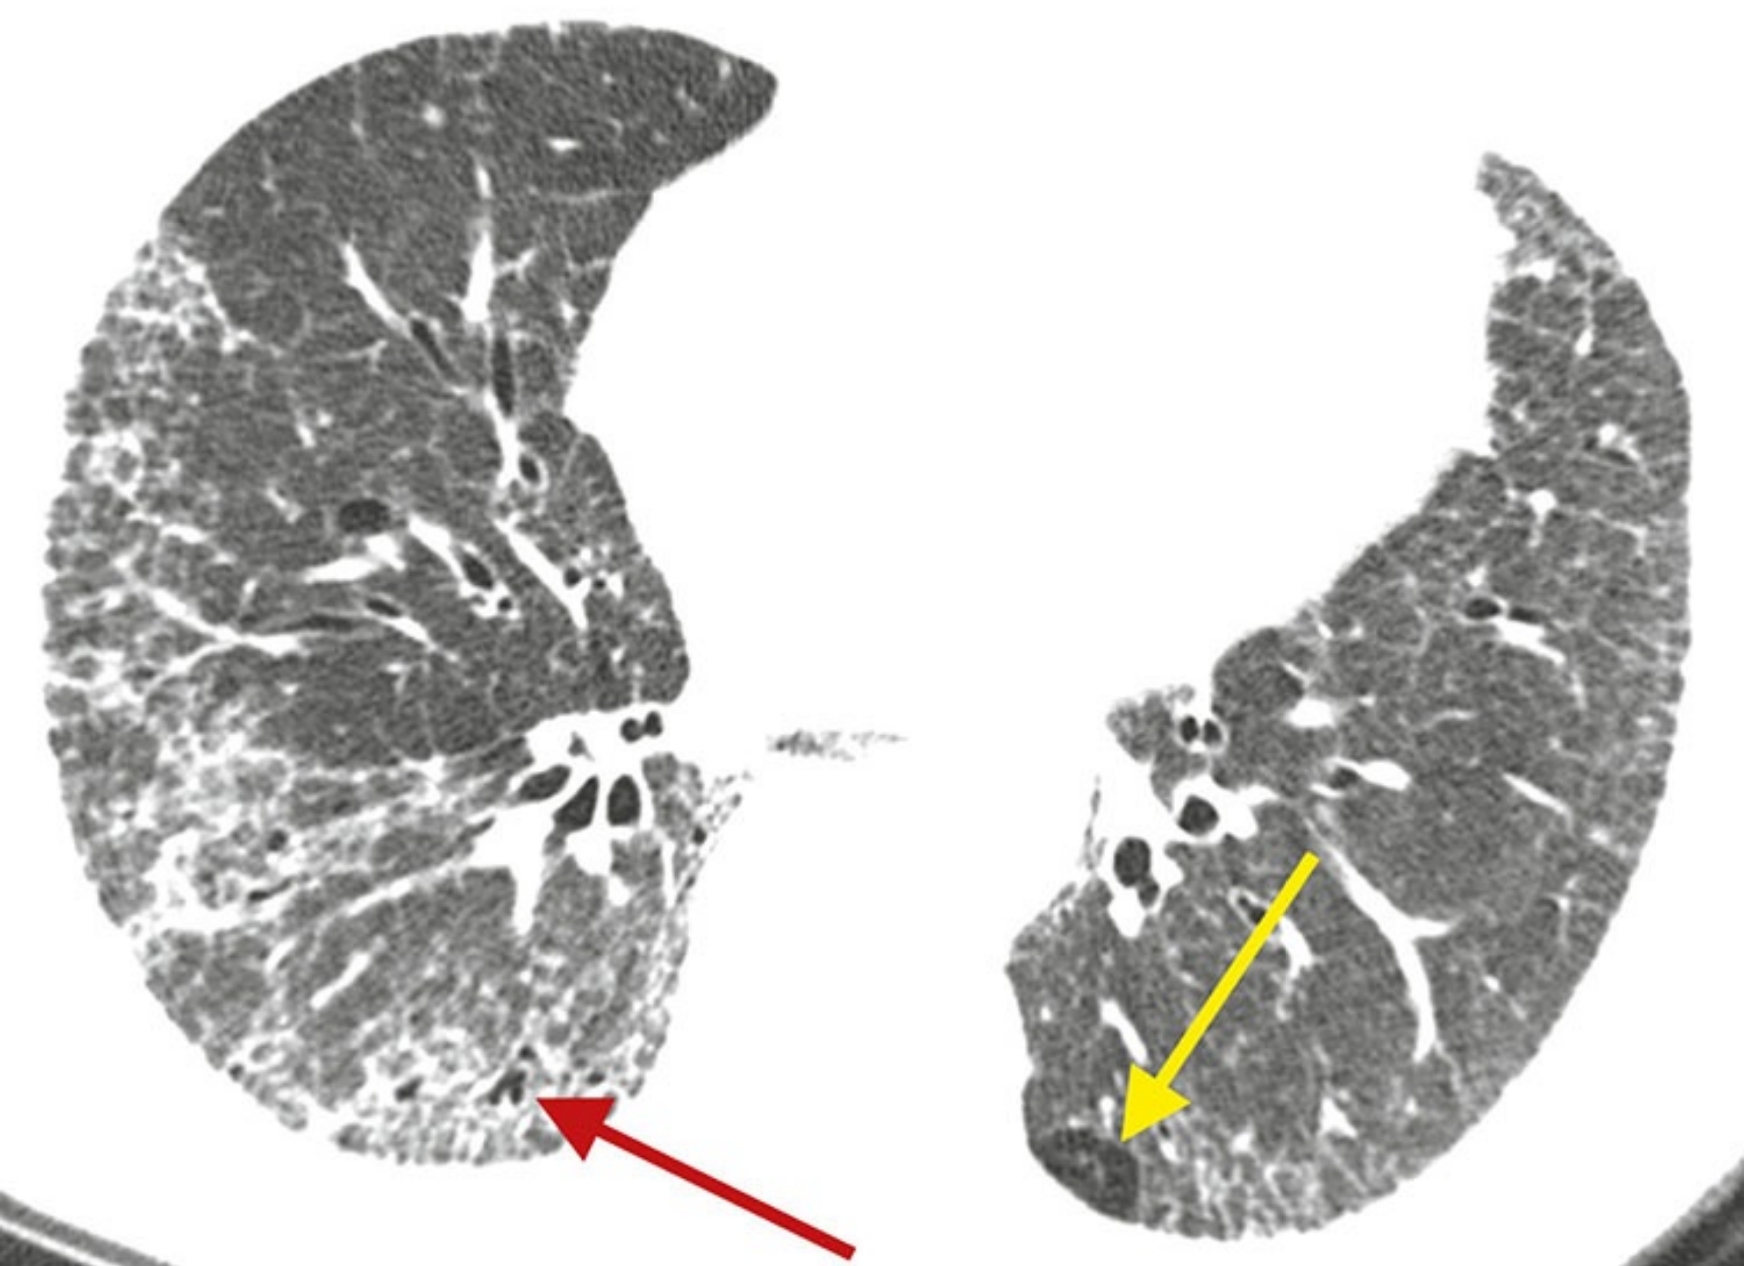

bd4645fb0627be9e02a166d0489509d6.jpg

特发性肺间质纤维化(IPF),不典型分布。

该IPF患者经肺活检证实为普通型间质性肺炎(UIP),其不典型表现为纤维化不以胸膜下分布为主而是明显累及肺中央区(A)。

另外,肋膈角相对不受累(B)。IPF的不典型征象不少见。从HRCT表现上看,本例可能被认为与UIP “相悖”。